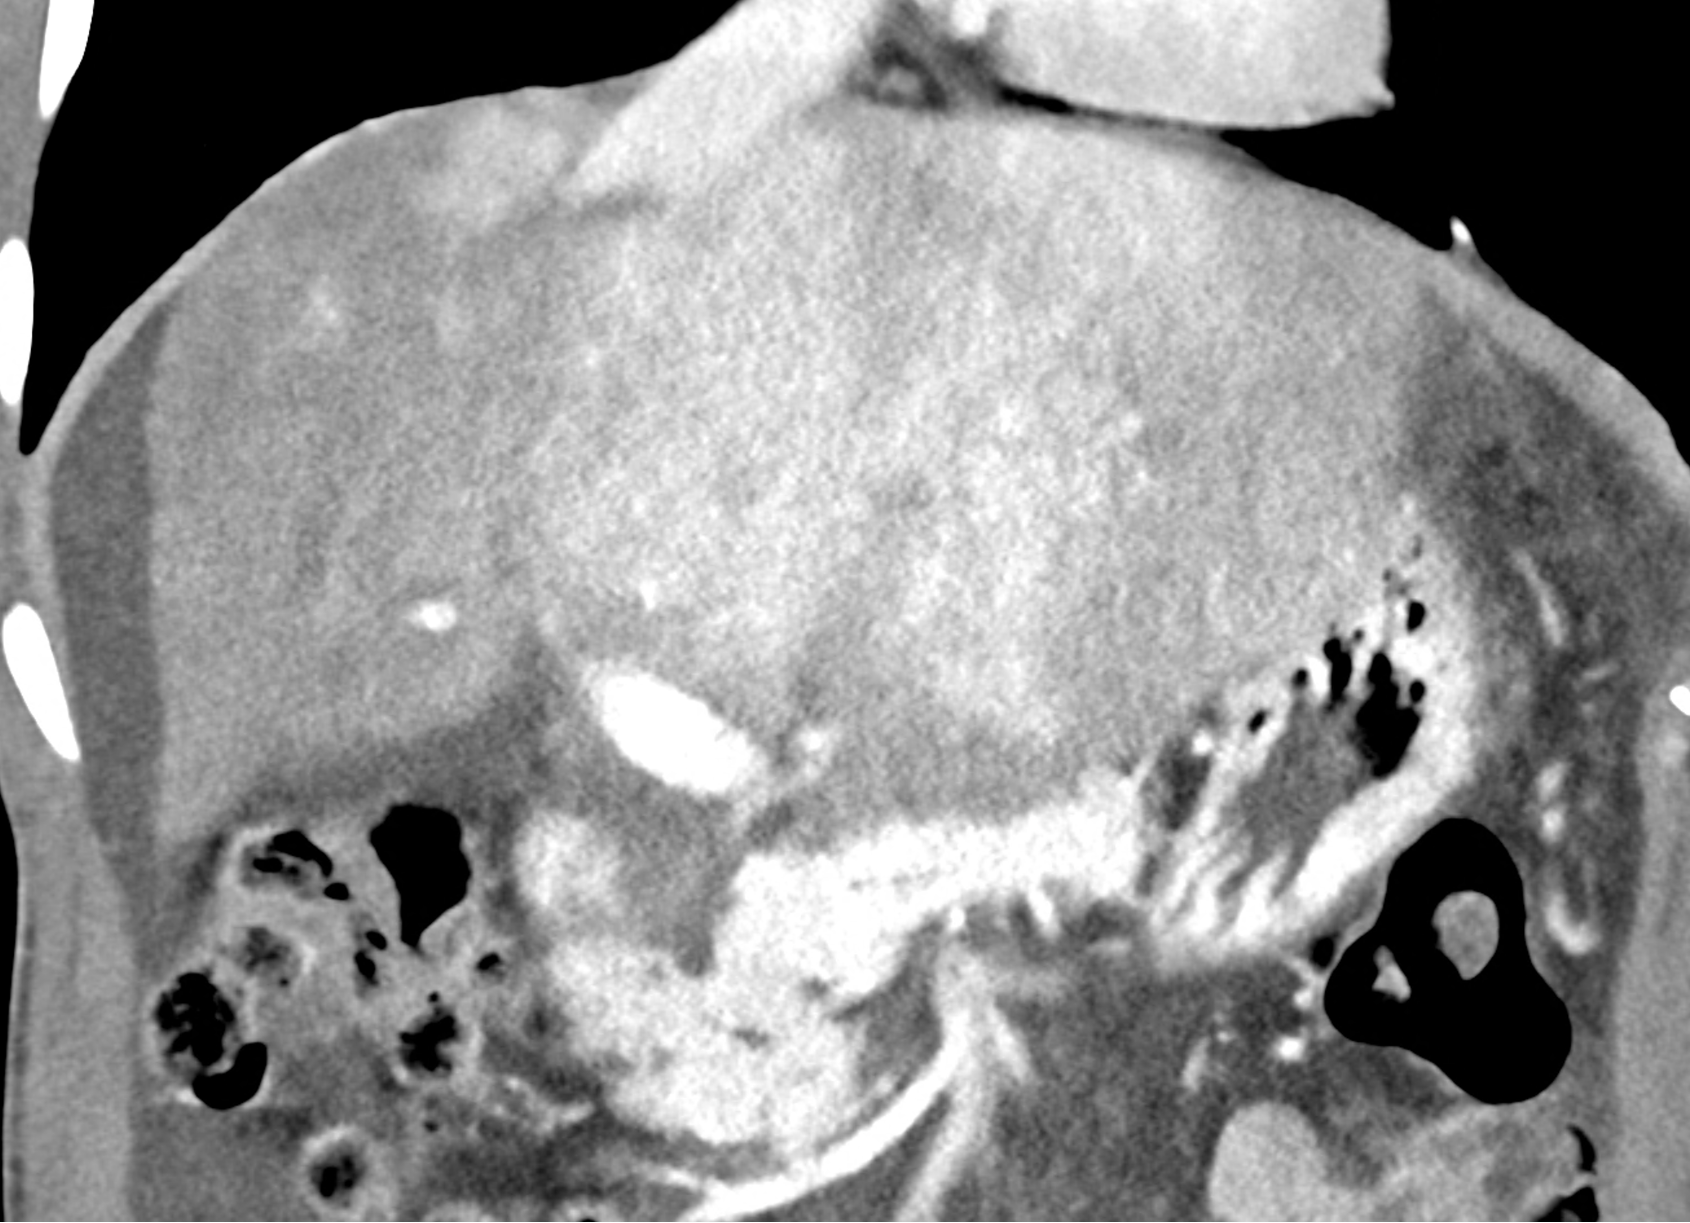

In CT images, BCS manifests as non-homogeneous enhancement of liver tissue in the arterial and especially in the portal phase, although in the portal phase may be increased, especially in the caudate lobe and left lobe, which are often hypertrophic (the hypertrophy and the enhancement is caused due to the possibility of the venous drainage directly into the inferior vena cava through the direct caudate veins), in contrast to the reduction in the right lobe. The portal vein is free, whereas even in the late phase, the hepatic veins and their contrast filling are not visible. Thrombotic occluded veins are hypodense.

A patient in his sixties with a Leiden mutation of factor V and a heterozygous prothrombin mutation presents with abdominal pain. Ultrasound examination reveals ascites and enlargement of the liver.There is enlargement of the liver, particularly the left lobe and caudate lobe. The hepatic veins are centrally filled with contrast medium due to reflux at the confluence with the inferior vena cava, and their radicular parts are thrombosed. There is typical chronic liver remodelling and the formation of centrifugal collateral circulation, including esophageal varices, and ascites is present in the abdominal cavity.

the axial images in the arterial, and the portal phases

coronary view documenting splenomegaly, different enhancement of the liver parenchyma, and ascites, the arterial, and the portal phases